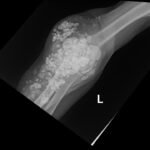

Calcinosis cutis is a condition in which calcium-phosphate salt deposits are formed in cutaneous and subcutaneous tissue. A subtype, metastatic calcinosis cutis, can occur in patients with disorders that cause hypercalcemia or hyperphosphatemia such as end stage renal disease. We present a case of a 67-year-old man with end-stage renal disease (ESRD) on dialysis who presented to the emergency department with a draining left elbow wound. On exam, he had irregular, firm nodules palpable in the subcutaneous tissue of both large and small joints. The presence of calcinosis cutis on imaging and lack of other findings suggesting infection led to outpatient wound care treatment. Recognizing the appearance of calcinosis cutis on imaging and conditions that present with calcinosis cutis is important for the emergency physician.